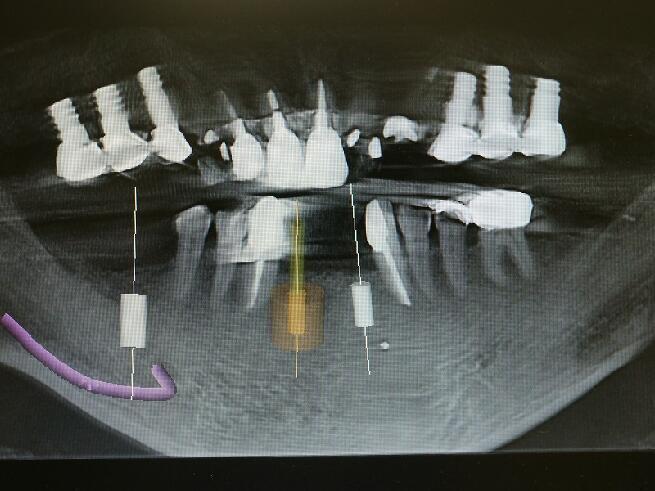

下顎の前歯の2番目の側切歯の位置へのインプラント埋入手術のCT写真上でシュミレーションして いるところです。3ミリのインプラント体を埋入するには骨が薄すぎます。ドリルでの切削では外側の壁に穴が開いたりドリルが突き抜けたりします。大変危険ですが多くの大学病院や歯科医院ではドリリングで対応してるのが現状です。 当医院では専用の器具を用いて対応しています。 前面から見た写真です(オレンジ色の部位です)